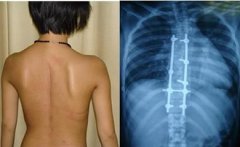

强直性脊柱炎是一种慢性的自身免疫系统的疾病,很多人都称强直性脊柱炎为不死的绝症。由此可以看见强直性脊柱炎的危害是有多严重,那么 强直性脊柱炎该如何治疗呢 ?下面贵阳风湿病中医院专家为您解答: 强直性脊柱炎不同时期的治疗方法 强直性脊柱炎早期的治...[详细] 2015-09-18